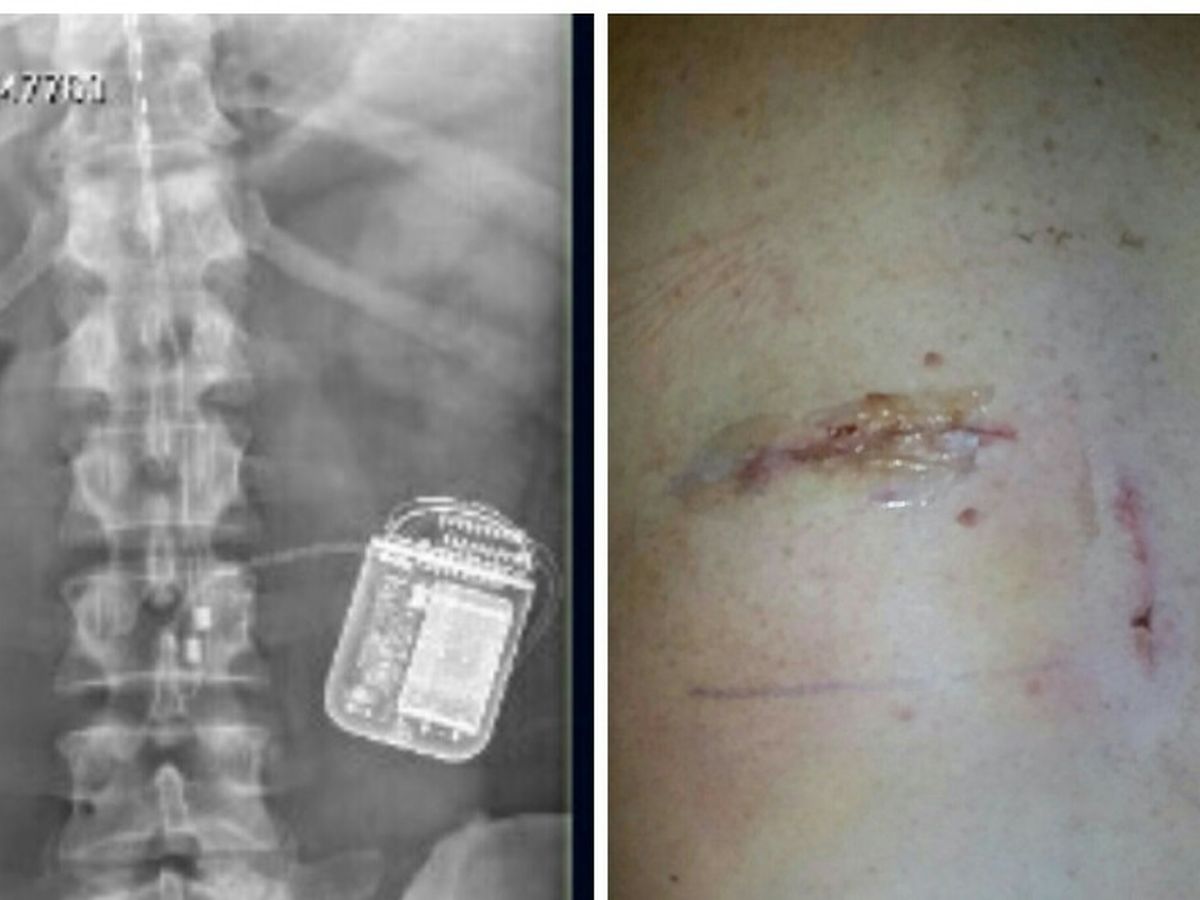

I was injured in August of 2015 during a drill weekend and my life has had some major changes. I suffered for about a year and half before doctors could give me a correct diagnosis (nerve damage). I then had surgery in February of 2017 to place a spinal cord stimulator in my back to try to help ease the pain level. The spinal cord stimulator (SCS) device was surgically placed under my skin (see photos) and it sends an electric current to my spinal cord. A small wire carries the current from a pulse generator to the nerve fibers of the spinal cord. When turned on, the SCS stimulates the nerves in the area where my pain is felt. I have to keep the device charged daily and I have went (and continue) through several changes in settings since having the device placed to try to find a comfortable setting for me to have enough comfort to function with limited capabilities. I deal with constant pain and discomfort in my back and legs on a daily basis. I have went from being a full-time, hard worker clocking in many long hours to not being able to do simple things like sitting for a long period or walking long distances. Even driving or riding to doctor's appointments cause me a lot of pain. I am constantly moving to try to find a comfortable position, I can not sit in a chair for very long, I need to adjust constantly to a laid back position with my feet up. I can not stand on my feet for very long either, I have to walk extremely slow when my back and leg are hurting. I am no longer able to work even part-time. I have no income coming in at all, my wife receives a very small portion (it is split 4 ways) of her Dad's pension from when he passed away. She is currently looking for work, with no luck so far. I received a letter from my mortgage company saying that I have until September 9th to be caught up with payments or I could lose my home. I currently owe $1,978.70, that is 3 months behind. I am also about to lose my car. I owe $825, it is also 3 months behind, to catch it up before they come and take it. I have used up all my resources that will help military people and I have emptied my saving's account. Creating this fundraiser is out of my comfort zone but my family comes before my pride. I am in a desperate situation which calls for desperate measures. I appreciate any help anyone can give at this time.